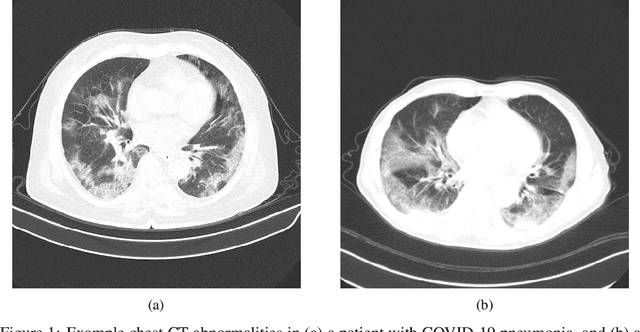

Abstract:The coronavirus disease 2019 (COVID-19) pandemic continues to have a tremendous impact on patients and healthcare systems around the world. In the fight against this novel disease, there is a pressing need for rapid and effective screening tools to identify patients infected with COVID-19, and to this end CT imaging has been proposed as one of the key screening methods which may be used as a complement to RT-PCR testing, particularly in situations where patients undergo routine CT scans for non-COVID-19 related reasons, patients with worsening respiratory status or developing complications that require expedited care, and patients suspected to be COVID-19-positive but have negative RT-PCR test results. Motivated by this, in this study we introduce COVIDNet-CT, a deep convolutional neural network architecture that is tailored for detection of COVID-19 cases from chest CT images via a machine-driven design exploration approach. Additionally, we introduce COVIDx-CT, a benchmark CT image dataset derived from CT imaging data collected by the China National Center for Bioinformation comprising 104,009 images across 1,489 patient cases. Furthermore, in the interest of reliability and transparency, we leverage an explainability-driven performance validation strategy to investigate the decision-making behaviour of COVIDNet-CT, and in doing so ensure that COVIDNet-CT makes predictions based on relevant indicators in CT images. Both COVIDNet-CT and the COVIDx-CT dataset are available to the general public in an open-source and open access manner as part of the COVID-Net initiative. While COVIDNet-CT is not yet a production-ready screening solution, we hope that releasing the model and dataset will encourage researchers, clinicians, and citizen data scientists alike to leverage and build upon them.